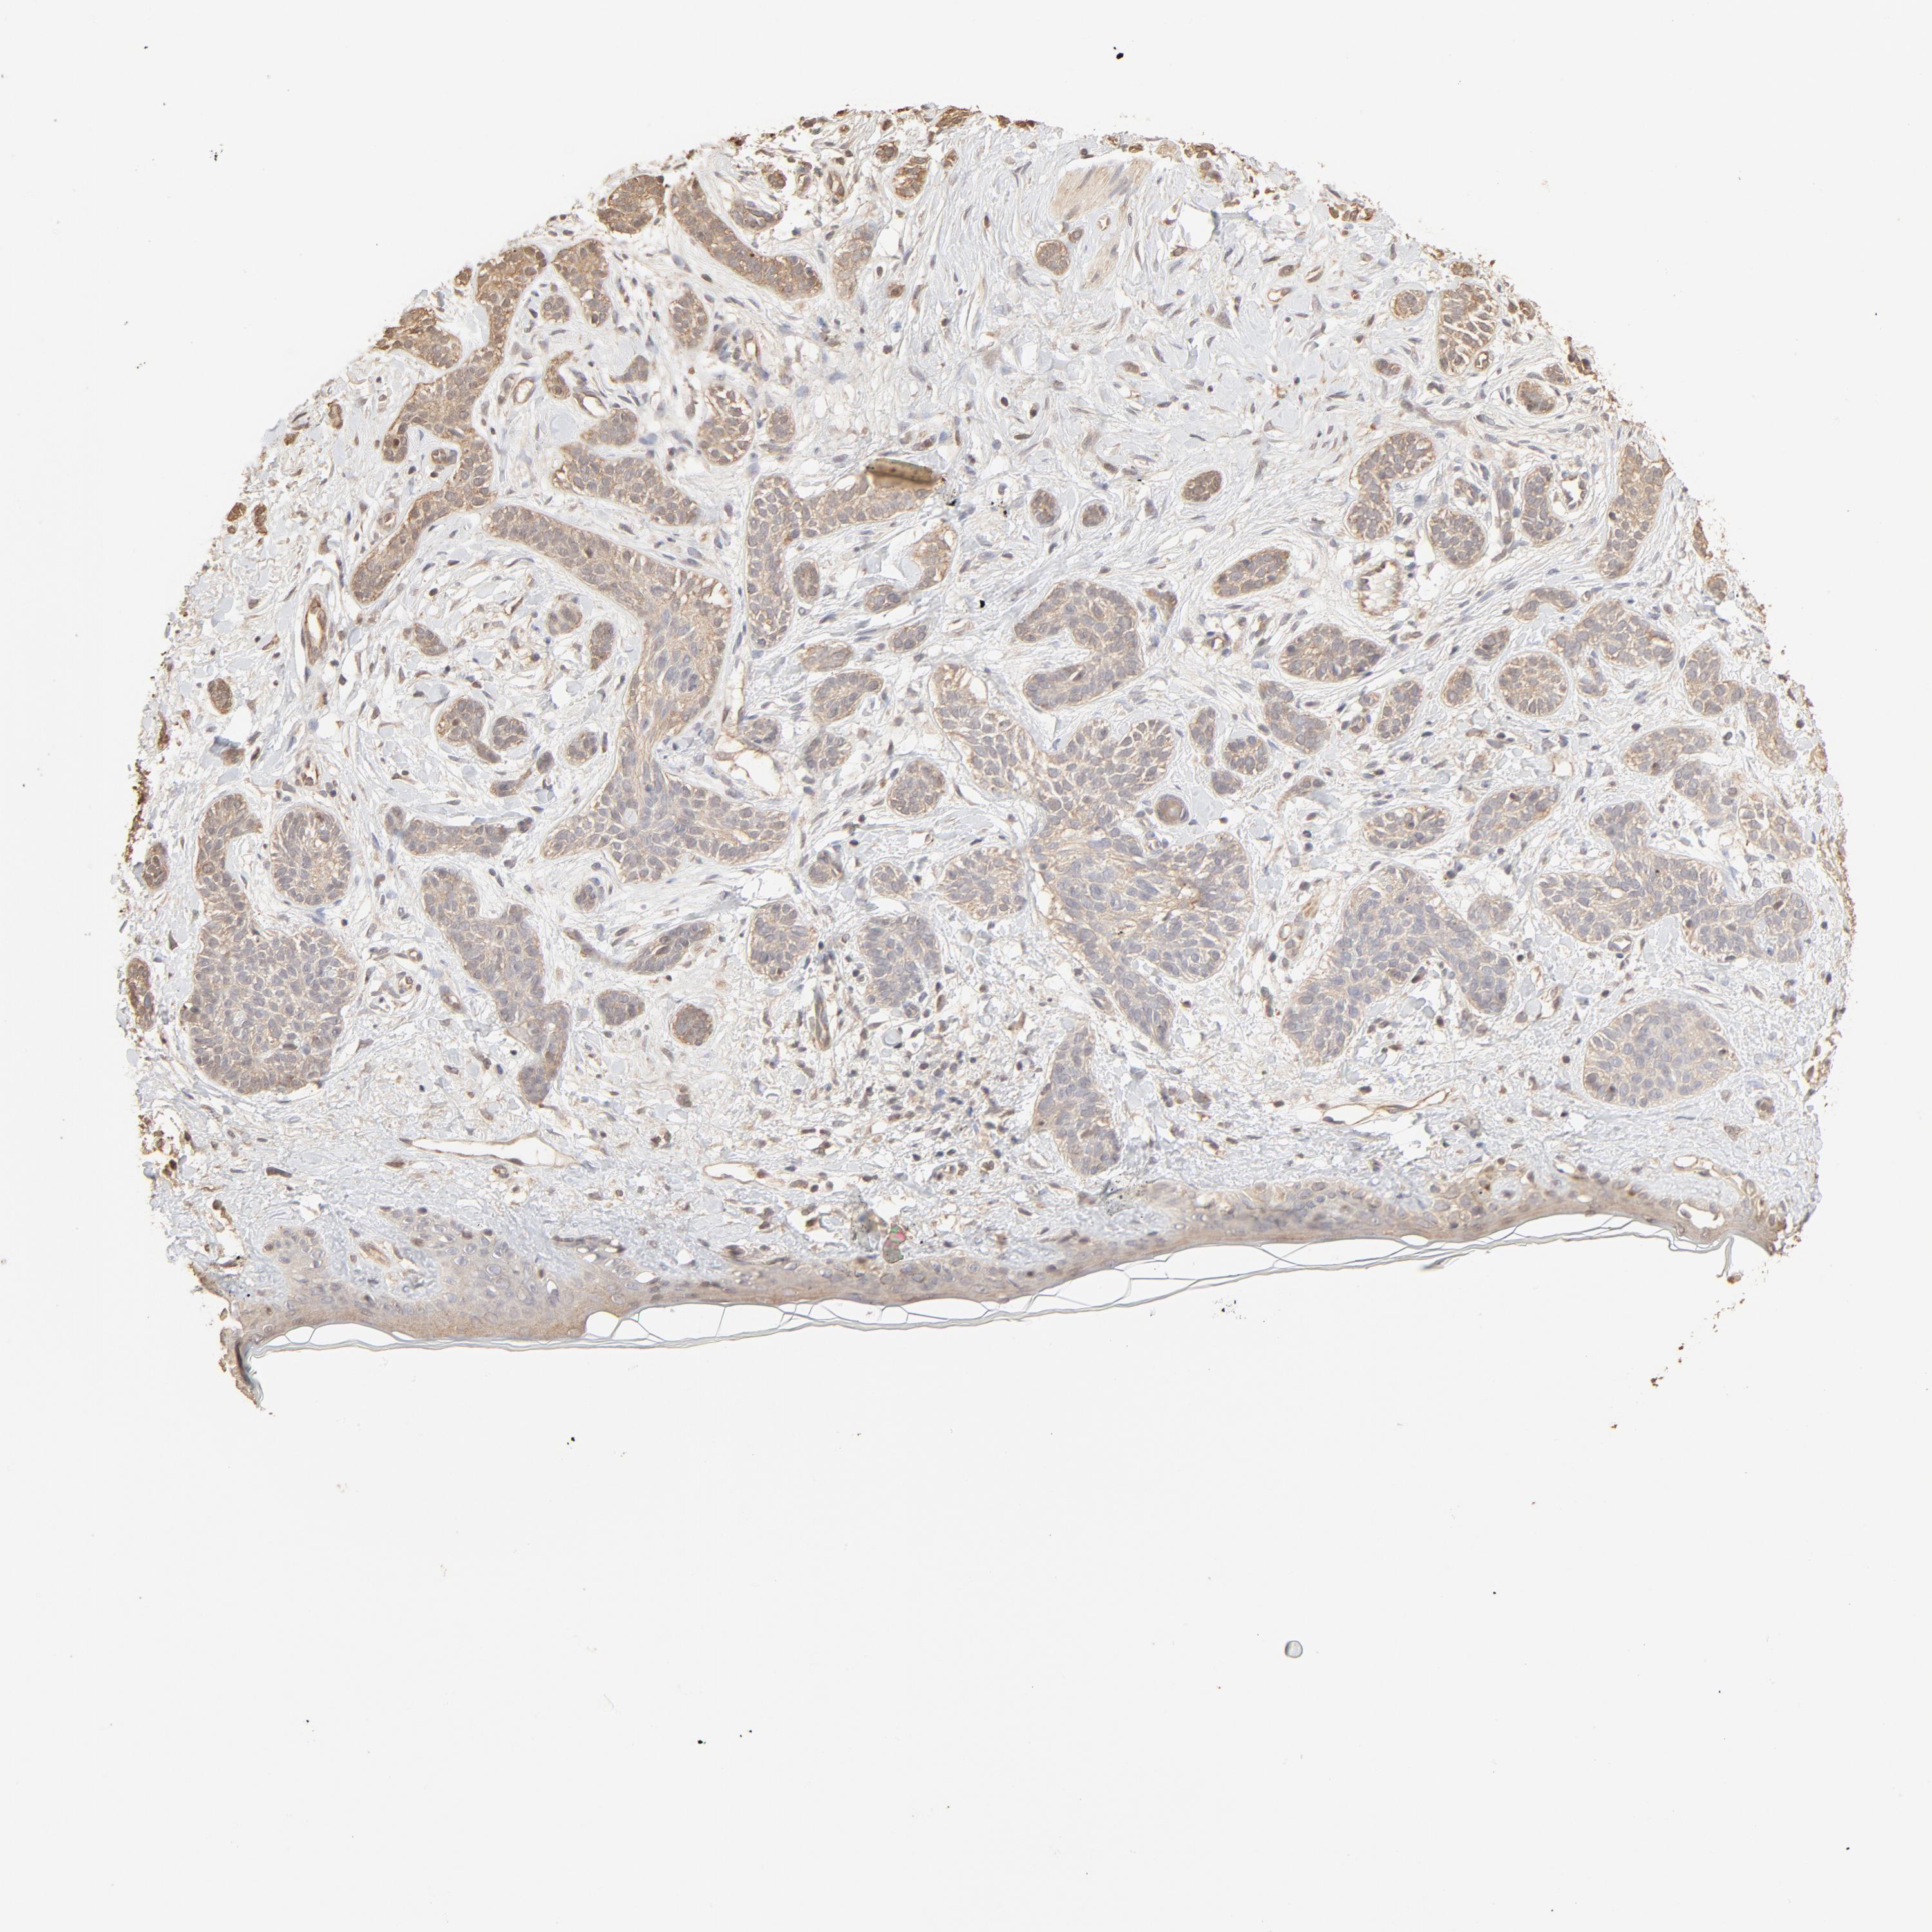

SKIN CANCER - Protein expressioni

A mouse-over function shows sample information and annotation data. Click on an image to view it in a full screen mode. Samples can be filtered based on level of antibody staining by selecting one or several of the following categories: high, medium, low and not detected. The assay and annotation is described here.

Antibody stainingi

Antibody staining in the annotated cell types in the current human tissue is reported as not detected, low, medium, or high, based on conventional immunohistochemistry profiling in selected tissues. This score is based on the combination of the staining intensity and fraction of stained cells.

Each image is clickable and will lead to virtual microscopy that enables deeper exploration of all samples and also displays staining intensity scores, fraction scores and subcellular localization as well as patient and tissue information for each sample.

Antibody HPA043236

Basal cell carcinoma